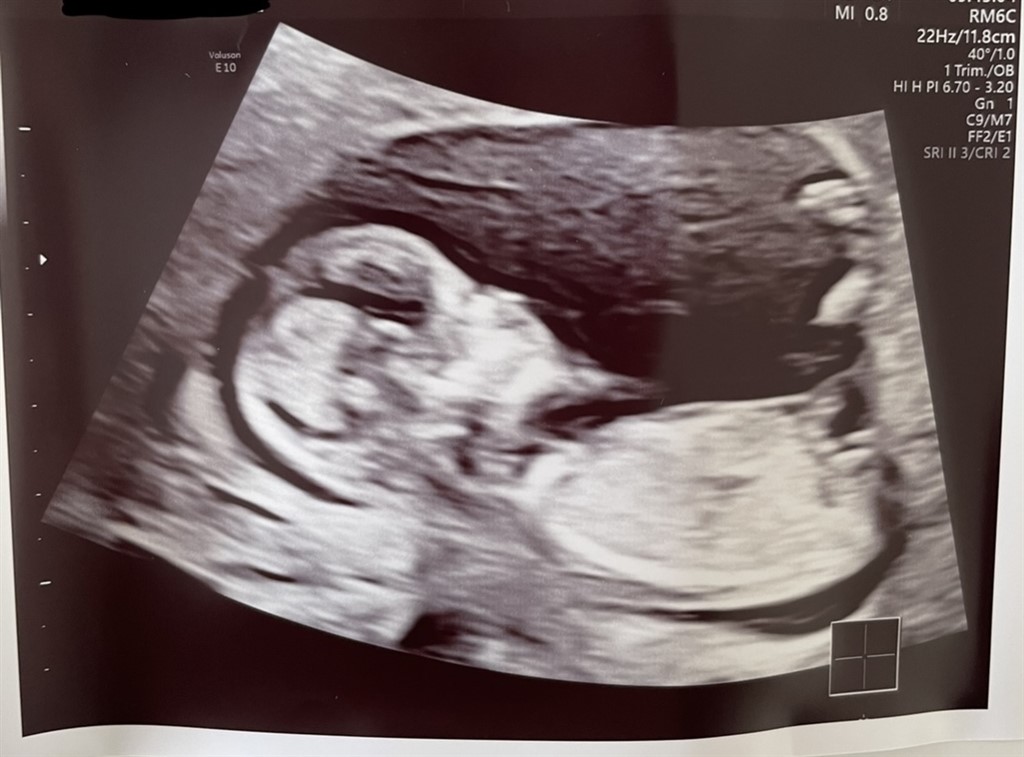

har været til vellykket NF scanning idag og 13+0  Jeg er så nysgerrig på køn, kan nærmest ikke vente de halvanden uge på en kønsscanning.

Er der nogen som er stærke i nub for jeg kan intet tyde ?

Vedhæftede fotos (klik for at se i fuld størrelse)

Næsten 100 procent sikker på det er en dreng

Jeg vil uden tvivl sige en pige.

Jeg vil heller ikke turde gætte på kønnet, synes ikke helt at nubben er så tydelig

Nå.. til vores store overraskelse venter vi os en lille aktiv dreng